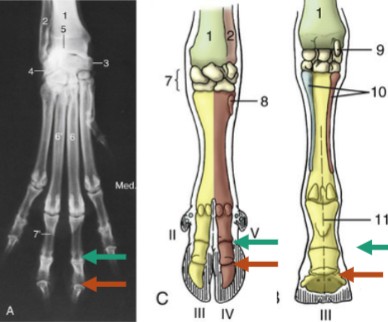

fetlock, hinge joint, between metacarpal bones and the proximal phalanges, where the proximal sesamoid bones lie, on the palmar side

teal, where P1 articulates with P2

orange, where P2 articulates with P3, where distal sesamoids lie